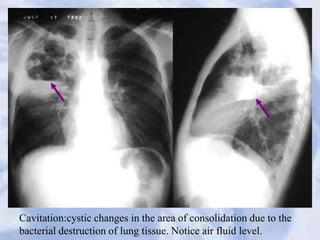

Cavitation:cystic changes in the area of consolidation due to the

bacterial destruction of lung tissue. Notice air fluid level.

Cavitation:cystic changes inthe area of consolidation due to the bacterial destruction of lung tissue. Notice air fluid level.